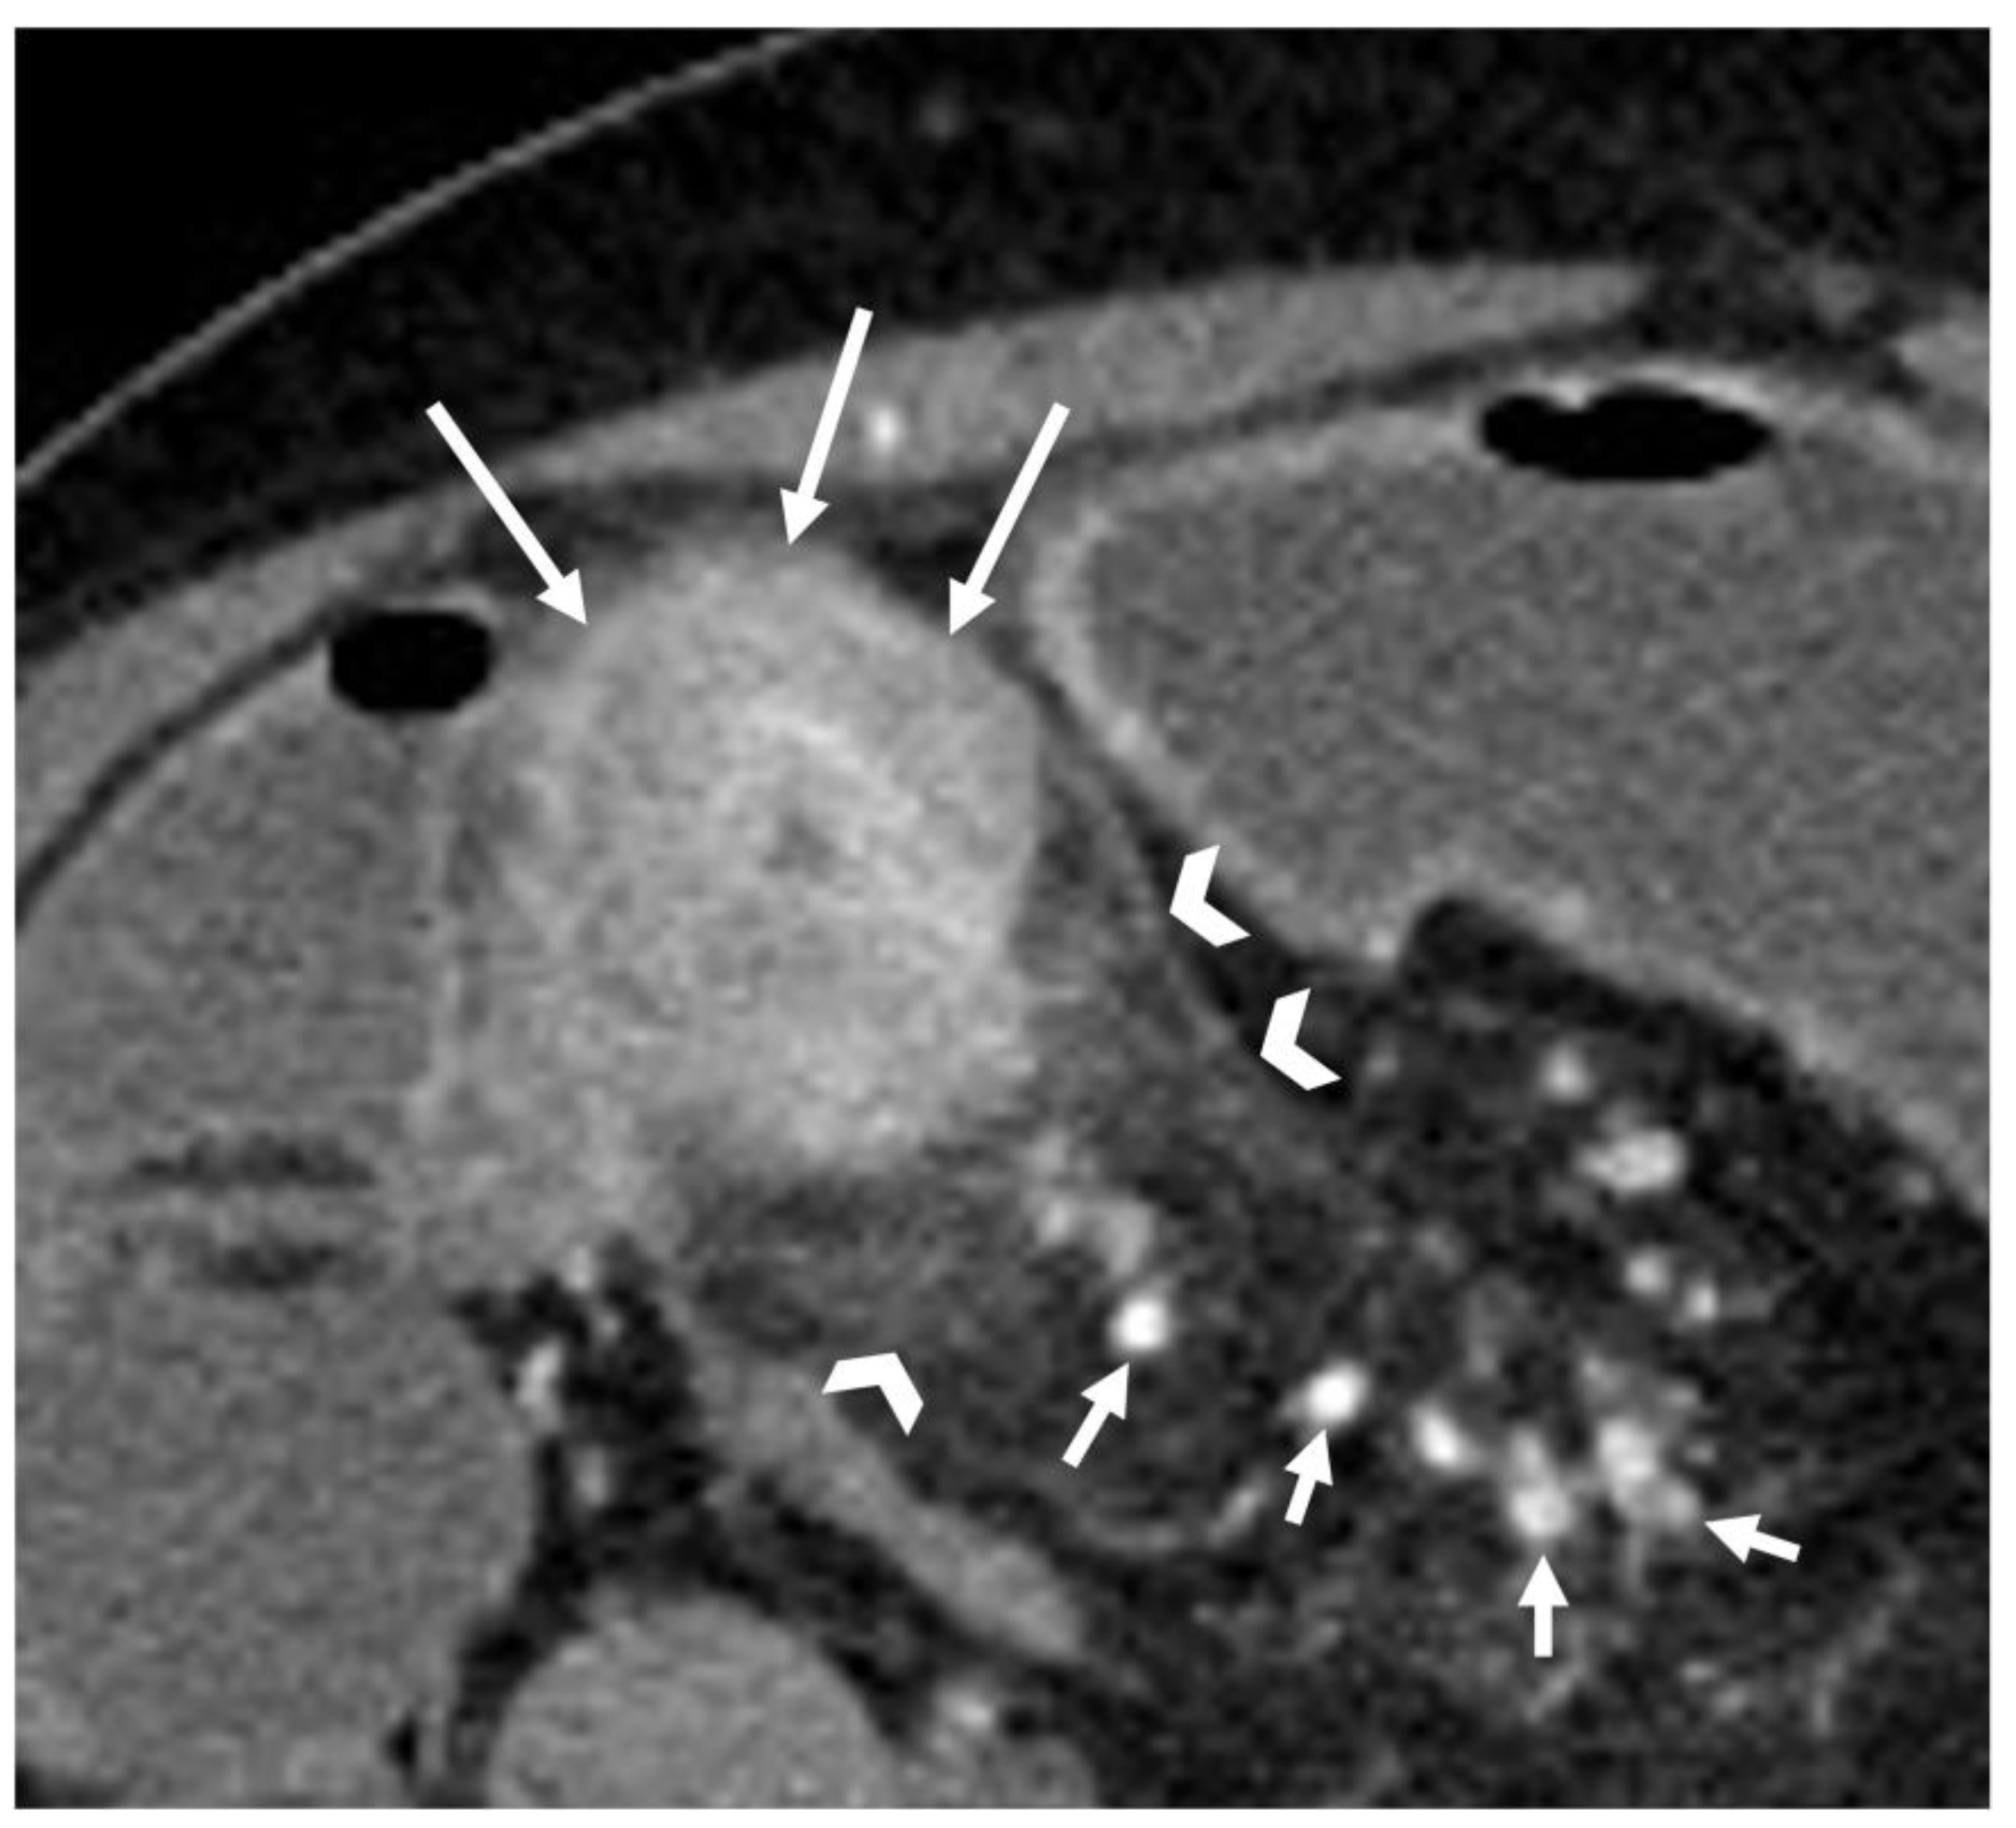

6. Is the Stricture Fibrotic or Inflammatory?